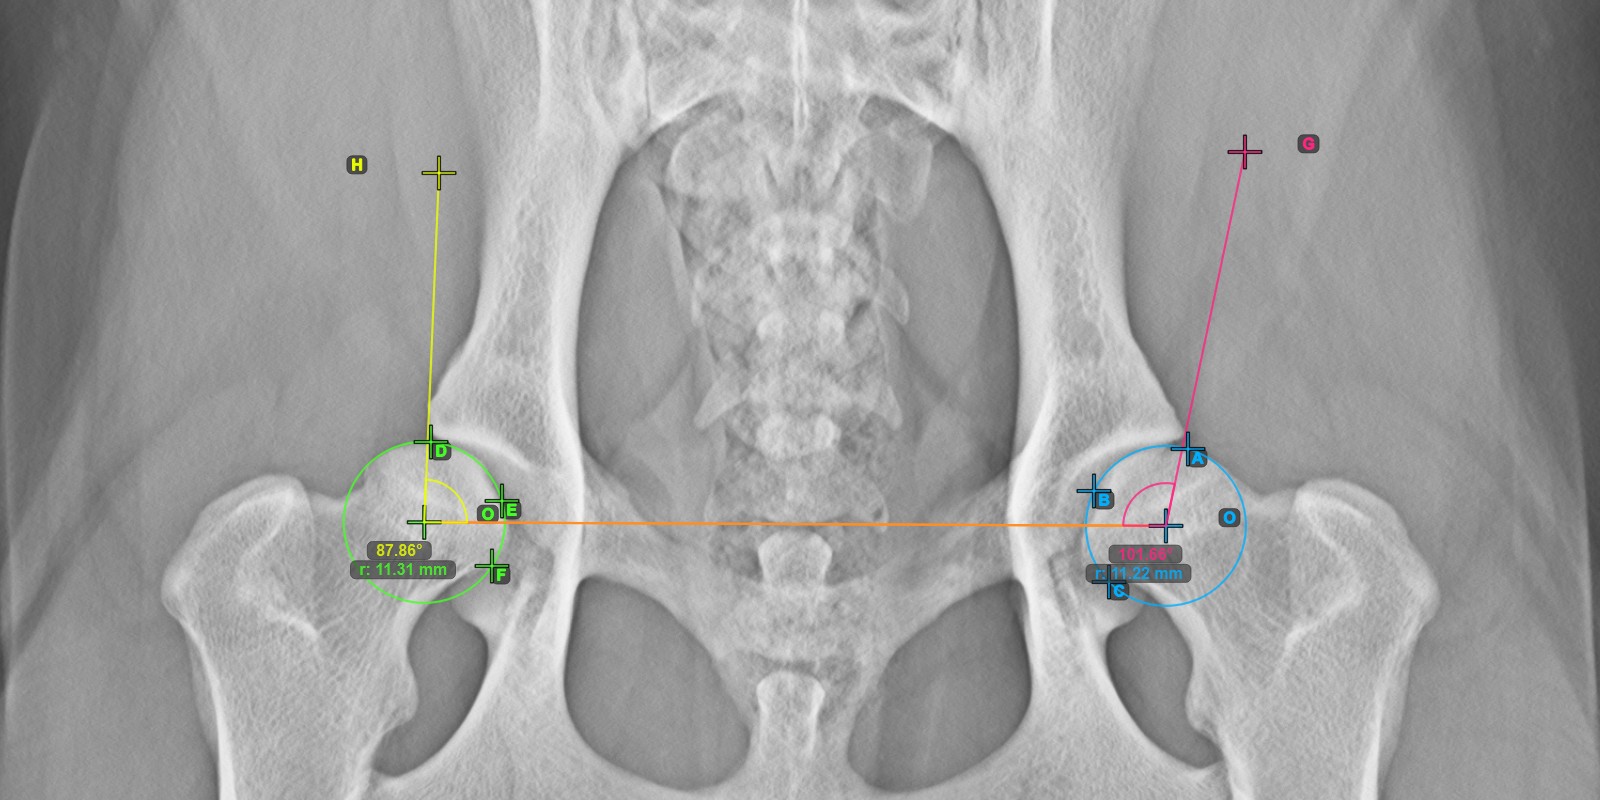

Calculate the left Norberg Angle measurement by marking a line on the effective edge of the left Acetabularis bone.

Mark a point near the left Caput Femoris and drag it along the effective edge of the left Acetabularis bone, forming the terminal side of the left Norberg Angle.

The drawn line must be a tangent to the effective edge of the left Acetabularis bone. The value and arc of the angle is automatically calculated.

The image below depicts the typical placement of the line and the calculated Norberg Angle measurement.